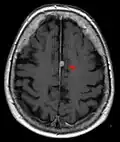

Cross-sectional T1-weighted MRI of a healthy human brain acquired with an ultra high-field MR of 7 Tesla field strength